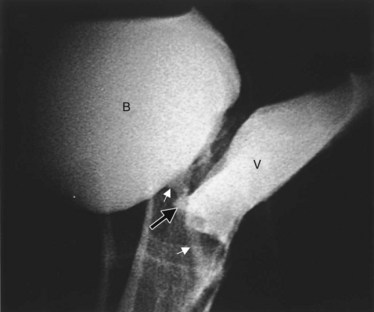

A cystogram and/or voiding cystourethrogram (VCUG) and an upper tract study should be performed in patients being evaluated for a VVF. The cystogram may objectively determine the presence and location of the fistula. Upon filling of the bladder, contrast often begins to opacify the vagina, almost immediately confirming the presence of a VVF. VVF are often best seen in the lateral projection (Fig. 77–7) in which the bladder and vagina are not superimposed. Often, the actual VVF tract may be visible in the lateral projection (Fig. 77–8). However, voiding images may be necessary in some patients with small fistulae, to demonstrate the VVF. The slight increase in intravesical pressure that accompanies micturition is usually adequate to demonstrate even very small fistulae. Importantly, a cystogram that fails to demonstrate a suspected VVF, but lacks voiding images or postvoid images, should be considered nondiagnostic. During voiding, care should be taken to exclude vaginal voiding or reflux of contrast from the introital region cephalad into the vagina, which would produce a falsely positive image. An involuntary bladder contraction can be provoked with rapid filling during cystography, and if the intravesical pressure rises sufficiently, this may also be sufficient to demonstrate a VVF when the filling images of the cystogram failed to demonstrate it. In some instances, a cystogram can also make an assessment of bladder capacity (important in the setting of prior radiotherapy), cystocele, bladder neck competence, and vesicoureteral reflux, any of which may have an impact on operative repair.

Step 2 (incision): The fistula tract is cannulated with a small Foley catheter (10 to 12 Fr) and, after inflation of the balloon, gentle downward traction is placed on the Foley catheter, pulling the VVF towards the introitus. Occasionally, a small VVF requires dilation with metal sounds to place the Foley catheter. To facilitate dilation of the fistula tract in these cases, a guidewire may be placed through the fistula tract endoscopically and sequential dilation performed using Goodwin sounds. The gentle traction on the VVF provided by the Foley catheter greatly enhances exposure (see Fig. 77–8). The vaginal flaps are marked (Fig. 77–13B). Saline is then injected into the anterior vaginal wall surrounding the fistula tract and along the lines of the vaginal flaps. The fistula tract is carefully circumscribed. An inverted J-shaped or U-shaped incision that circumscribes the fistula tract is made with the limbs of the J or U extending to the apex of the vagina. The circumscribed fistula is incorporated into the curved portion of the incision. The nature of this incision allows creation of a vaginal wall flap that can be advanced and rotated over the fistula repair. This helps avoid vaginal shortening and overlapping of suture lines during reconstruction. However, some surgeons have recommended that the long end of the incision be extended along the anterior vaginal wall toward the introitus (Wang and Hadley, 1990).